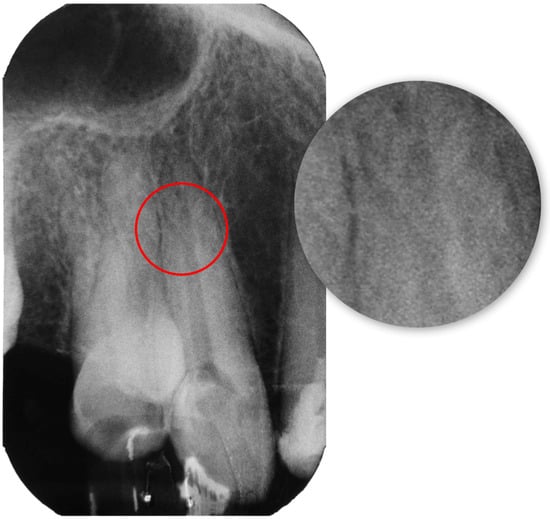

2.1. Report A